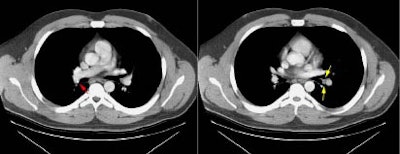

Example 1: This is an example of an N1 node in a patient with a lingular adenocarcinoma (left image). Although not pathologic by short axis size criteria, the lymphatic tissue in the left hilum has a convex border with the adjacent lung (white arrows). This node contained adenocarcinoma at histopathologic analysis. Some authors advocate using the presence of a convex margin of the interstitium with the lung parenchyma to indicate pathologic adenopathy to improve the sensitivity of CT for detecting hilar metastases [36].

Example 2: This patient is an example of a false negative CT for hilar nodal metastases even when applying the suggested new criterion. The patient had a peripheral adenocarcinoma in the left upper lobe (black arrows). The left hilar node (yellow arrows) is not pathologic by size criteria, nor does it exhibit a convex margin with the adjacent lung parenchyma. This is a normal node by CT, however, at histopathologic analysis the node was positive for malignant cells.